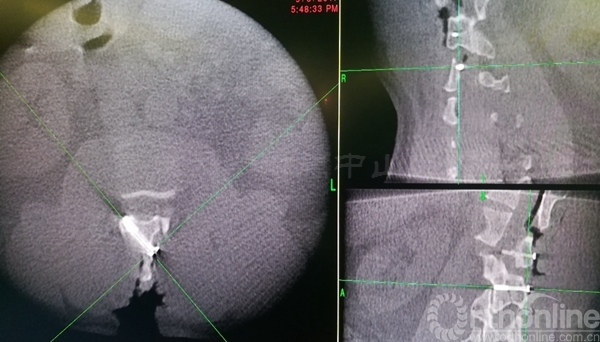

术中椎板截骨行肿瘤切除后,椎板回植术,回植椎板采用空心螺钉固定

术后肌力恢复至4+级,无脑脊液漏,X线片及CT平扫显示椎板回植位置满意,空心钉固定牢靠。术后病理诊断为脊膜瘤伴细胞丰富

术后三个月患者腰背痛完全缓解,肌力已恢复至5级,下肢麻木感消失。CT显示:椎板截骨面已骨性愈合,无移位,椎管容积与术前无明显差异

术后半年CT显示两侧椎板截骨面均已骨性愈合,椎管体积无减少。MRI显示椎管内脊膜瘤无复发